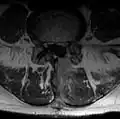

Hemilaminektomie

Hemilaminektomie

Bei dieser Operation wurde der gesamte Wirbelbogen auf der betroffenen Seite entfernt. Der Spinalkanal ist nicht mehr gut einsehbar, hier ist Blut eingedrungen -

Nukleotomie

Nukleotomie

Hier das gleiche Bild, zur besseren Übersicht ohne eingebauten Text. Sehr deutlich ist das Narbengewebe zu sehen, das sich neben dem Dornfortsatz bis an den Wirbelbogen bildet